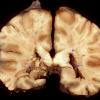

Meningitis

Meningitis, acute (2)